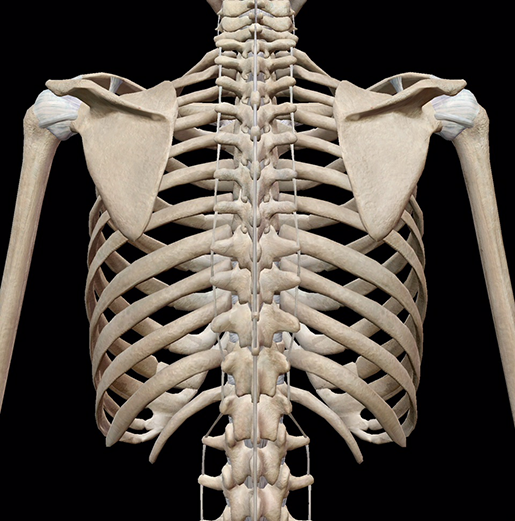

Верхняя часть панциря – это грудная клетка, отмечает эксперт. Рёбра у черепахи сливаются вместе там, где расположен позвоночник, и образуют панцирь. То есть они как бы простираются вокруг плеч и таза животного. Похожим образом устроены рёбра у человека.

Нижняя же сторона панциря – это плечевой пояс и грудина черепахи. Вместе с тем сам панцирь состоит не только из костей, но и из пластин роговидного кератина. Они защищают панцирь от стирания и обеспечивают гидроизоляцию (защита от влаги).